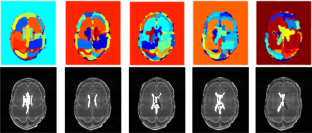

White matter injury (WMI) is the most prevalent brain injury in the preterm neonate leading to developmental deficits. However, detecting WMI in magnetic resonance (MR) images of preterm neonate brains using traditional WM segmentation-based methods is difficult mainly due to lack of reliable preterm neonate brain atlases to guide segmentation. Hence, we propose a segmentation-free, fast, unsupervised, atlas-free WMI detection method. We detect the ventricles as blobs using a fast linear maximally stable extremal regions algorithm. A reference contour equidistant from the blobs and the brain-background boundary is used to identify tissue adjacent to the blobs. Assuming normal distribution of the gray-value intensity of this tissue, the outlier intensities in the entire brain region are identified as potential WMI candidates. Thereafter, false positives are discriminated using appropriate heuristics. Experiments using an expert-annotated dataset show that the proposed method runs 20 times faster than our earlier work which relied on time-consuming segmentation of the WM region, without compromising WMI detection accuracy.

Fig. 3